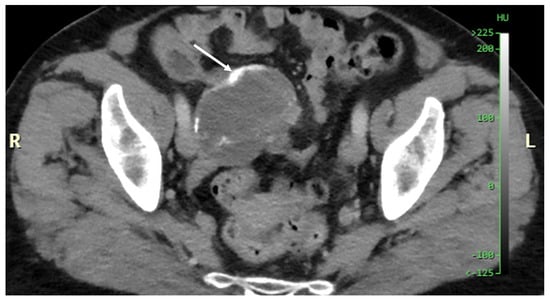

Figure 11. CT, venous phase, axial plane.

Figure 11, Figure 12, Figure 13, Figure 14 and Figure 15. Advanced stage of the disease. The abdomen is full of tumors and mucin. Typical signs are heterogeneous or hypodense masses in the form of lobules often with septa, which could be enhanced by contrast and could be associated with calcifications.

Patients with a misdiagnosed rupture of the mucocele may develop pseudomyxoma peritonei. It is characterized by the presence of an abundant gelatinous substance in the abdomen. Diffuse, progressive, and abundant mucin-containing tumor cells are typical of this disease [2] (Figure 11, Figure 12, Figure 13, Figure 14, Figure 15 and Figure 16). The interval between rupture and advanced disease is several years. In our clinical series, the interval was about 5 years. In the literature, we found a wide range of this interval from 12 months to 10 years [9,10]. The natural history of PMP revolves around the “redistribution phenomenon”, whereby mucinous tumor cells accumulate in the Douglas pouch, in the diaphragm (more on the right), and the small and large omentum (Figure 17). The small intestine is less involved [4]. Pseudomyxoma peritonei is a slowly progressing disease, which fills the peritoneal cavity over time. There are several classifications of pseudomyxoma. The most commonly used is the PSOGI classification [2]. Mucinous accumulation progresses to malnutrition, bowel obstruction, and respiratory compromise. Rarely, the tumor may spread to the pleural cavity. This has been described in 5.4% of cases. It may occur spontaneously or as a result of diaphragmatic injury during cytoreduction [8,11].